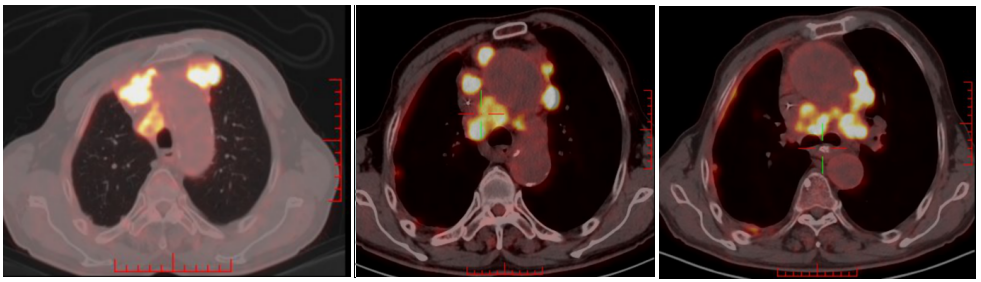

2022-06-28日复查PET-CT:1、双侧头臂血管周围、右侧气管食管沟、纵隔(2R、2L、3a、4R、4L、5、6、7区)右侧肋膈角见多发FDG代谢增高淋巴结,部分淋巴结坏死,结合病史,考虑多发淋巴结转移,病变数目较前增多、体积增大。L3椎体右侧、左侧肩胛冈FDG代谢增高,考虑骨转移。2、右肺上叶前段胸膜下环形FDG代谢增高病变中心伴有坏死,病变较前稍增大;左肺上叶舌段及下叶内前基底段、右上叶及下叶多发结节,部分伴FDG代谢增高,较前未见明显变化;右侧胸膜增厚伴右侧胸膜增厚伴FDG代谢增高,较前增厚,右侧胸腔积液较前减少。余未见转移征象。综上:多发淋巴结转移,新发骨转移,考虑PD。